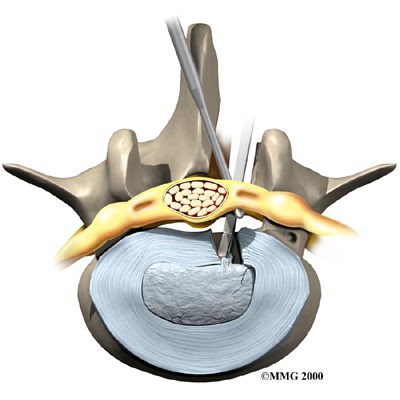

Microdiscectomy

Microdiscectomy is becoming the standard surgery for lumbar disc herniation. The procedure is used when a herniated disc is putting pressure on a nerve root. It involves carefully taking out part of the problem disc (discectomy). By performing the operation with a surgical microscope, the surgeon only needs to make a very small incision in the low back. Categorized as minimally invasive surgery, this surgery is thought to be less taxing on patients. Advocates also believe that this type of surgery is easier to perform, that it prevents scarring around the nerves and joints, and that it helps patients recover more quickly.

Related Document: FYZICAL Copperfield's Guide to Lumbar Discectomy